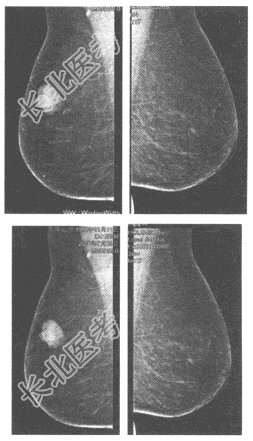

- 单项选择题患者,女性, 78岁,右乳腺触及肿物1周, 乳腺钼靶图像如下,最可能的诊断为

A、乳腺纤维腺瘤

B、乳腺增生结节

C、乳腺导管内乳头状瘤

D、急性乳腺炎

E、乳腺癌